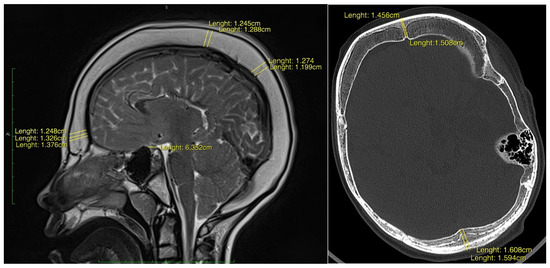

3.2. Calvarial Thickening and Morphometry

Quantitative morphometric analysis demonstrated generalised calvarial hyperostosis in all patients (Table 2). Mean frontal bone thickness at the glabellar region was 12.77 mm (SD ± 3.07), representing a 2.1-fold increase relative to age-matched paediatric norms. Parietal bone thickness at the vertex was 11.13 mm (SD ± 2.68), corresponding to a 1.85-fold increase, and occipital bone thickness at the lambda measured 12.21 mm (SD ± 2.36), equating to a 2.02-fold age-adjusted thickening. The overall mean calvarial thickness across all measured regions was 12.04 mm (SD ± 2.70), confirming a diffuse and significant increase in cranial vault thickness (Figure 1).

Figure 1. (left) Sagittal T1-weighted post-contrast MR image of a 16-year-old male demonstrating diffuse inner-table calvarial thickening. The patient underwent ventriculoperitoneal shunt placement at 2 months of age for obstructive hydrocephalus secondary to a neoplastic process. The mean calvarial width at glabellar point measures 13.2 mm, and at vertex 12.4 mm. (right) Axial CT image in bone window of a 13-year-old female demonstrating generalised vault hypertrophy, most pronounced within the frontal and occipital bones. A ventriculoperitoneal shunt was inserted at 1 month of age following severe intraventricular haemorrhage. The mean calvarial width at glabellar point measures 14.8 mm, and at lambda 15.9 mm.